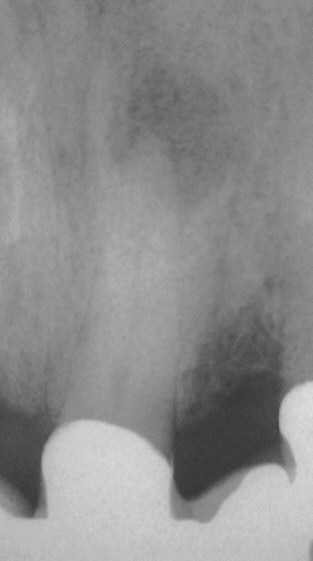

Zahn 21 im März 1997, 8 Monate nach Zementierung einer 6-gliedrigen Brücke (Klick!)

Unmittelbar nach WF im April 1997 (Klick!)

Oktober 1998 (Klick!)

November 2002 (Klick!)